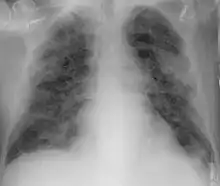

Imaging

Chest CT scans may be helpful to diagnose COVID‑19 in individuals with a high clinical suspicion of infection but are not recommended for routine screening.[159][171] Bilateral multilobar ground-glass opacities with a peripheral, asymmetric, and posterior distribution are common in early infection.[159][172] Subpleural dominance, crazy paving (lobular septal thickening with variable alveolar filling), and consolidation may appear as the disease progresses.[159][173] Characteristic imaging features on chest radiographs and computed tomography (CT) of people who are symptomatic include asymmetric peripheral ground-glass opacities without pleural effusions.[174]

Many groups have created COVID‑19 datasets that include imagery such as the Italian Radiological Society which has compiled an international online database of imaging findings for confirmed cases.[175] Due to overlap with other infections such as adenovirus, imaging without confirmation by rRT-PCR is of limited specificity in identifying COVID‑19.[174] A large study in China compared chest CT results to PCR and demonstrated that though imaging is less specific for the infection, it is faster and more sensitive.[158]